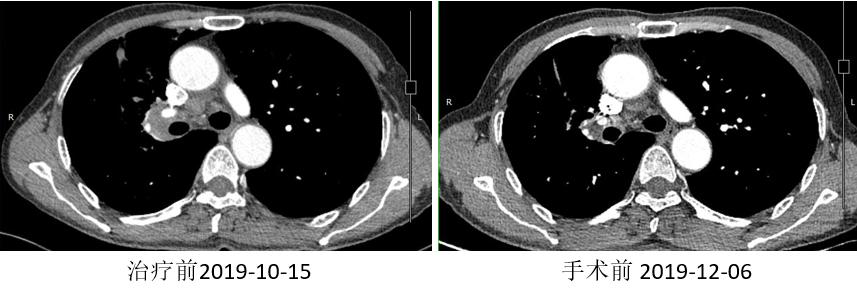

胸部CT

外周淋巴结CT

2019.12.03 行“VATS辅助切口左肺上叶袖式切除术”。

术后病理:(左上叶)未见肿瘤细胞残留。病灶内大片区域纤维化伴胶原化,组织细胞积聚,淋巴细胞浸润,病灶周边见个别多核巨细胞反应,符合化疗后表现(疗效PCR)。第6、7组淋巴结见钙化灶,未见癌细胞。肺门支气管旁淋巴结未见癌细胞,见纤维组织增生伴胶原化及黑色颗粒沉积。

疗效评价:pCR(病理完全缓解:原发灶和淋巴结手术标本病理检查无浸润性肿瘤细胞残余)。